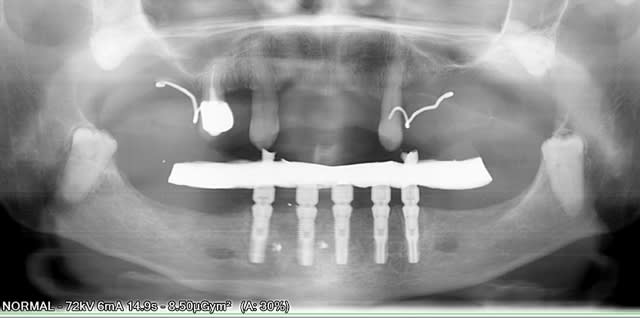

Alors voilà: empreinte pick-up mixte (silicone et plâtre snowhite), RIM avec cire calée sur des piliers hauts, et aujourd'hui retrait des implants provisoire et vissage de la prothèse.

Belle cicatrisation osseuse en distal de H1.

il se trouve que la parallélisme des implants était tel que j'ai pu me passer des piliers multi. L'empreinte au plâtre est sortie sans forcer et l'insertion ce matin à la pose s'est faite de même (je pensais à l'extrême limite devoir shorter un peu les bords des hexagones, mais même pas), juste au dessus des hexagones on a une liaison conique à 11°. Une prothèse est déjà réalisée tout en résine et incluant les piliers usinés, puis la résine est évidée en lingual, une maquette en cire est réalisée en épousant le plus possible les piliers. Elles est ensuite coulée, adaptée contre les piliers et enfin soudée au laser avec apport de cobalt conte les piliers....la passivité est conservée. Maintenant, c'est la première fois que je n'utilise pas les piliers multi, ici c'est assez par hasard que les implants aient été parallèles. c'est vrai que le coût en a été moindre mais ce n'était pas l'objectif premier.